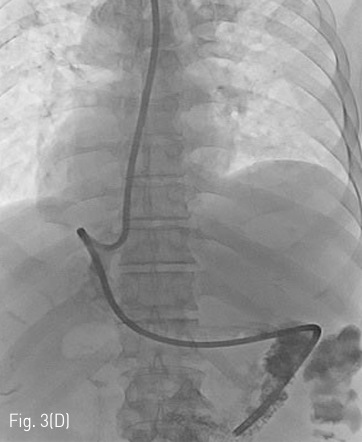

Fig 3D

(D) After sufficient dilatation, the dilator is removed to leave only the J-tip guidewire and the external sheath in place. A 14Fr jejunostomy catheter is then inserted over the J-tip guidewire via the external sheath. After removing the guidewire, contrast medium is injected into catheter to confirm that the tip of the tube was placed appropriately.